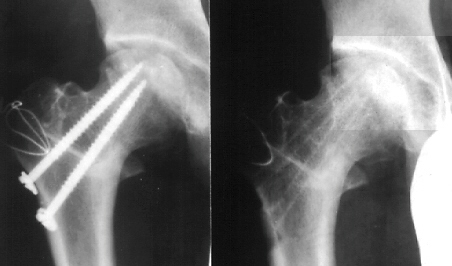

Sugioka's rotational osteotomy was advised. Pre-operative range

of motion was flex.90, abd.35, e.r. 40, and i.r. 15. The femoral

head was anteriorly rotated by 75 degrees and varus angulation

by 15 degrees was made.

Continuous-passive-motion and pulley exercise on a bed was started

from the 1st post-operative day. Skin traction was performed for

2 weeks. After post-operative non-weight-bearing for 4 weeks,

and partial-weight-bearing for 6 weeks, he has had neither limping

nor pain for more than 3 years.

- Two large pins are inserted parallel into proximal and distal

fragments, and femoral head is rotated anteriorly by handling

proximal pin.

- After adequate rotation, a large screw is inserted in valgus

position. An A-P X-ray should be taken to ensure the weight-bearing

portion is well apposed and the neck-shaft angle. Then a Steinman

pin is removed and another large pin is inserted. The A-O compression

screw is ineffective because of its thin shank.

- The intentional varus position may be made in addition to

anterior rotation for an extensive lesion.